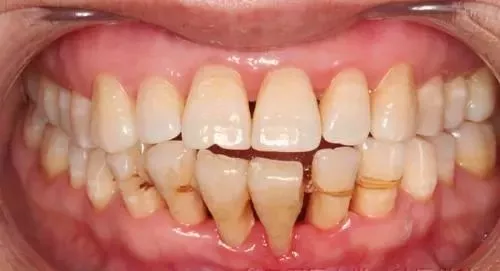

症状3:牙龈萎缩

牙龈萎缩也是牙周炎的症状之一,但患者常不易察觉。由于长时间受大量牙石的压迫,刺激牙龈。所以,龈缘外形出现水平式的退缩。至于老年性的牙周组织退缩,一般属于正常的生理退缩。

一方面是因为牙周组织本身的退缩;另一方面是由于牙齿的磨耗而使牙齿继续萌出,形成牙根面暴露。由于牙根面的暴露,对冷、热、甜、酸食物或机械性刺激,均有敏感的表现。